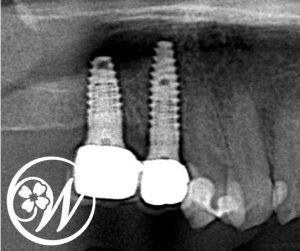

精密検査(レントゲン・CT)を行った結果、右上5番は残根状態で保存が困難、さらに右上6番はすでに欠損している状態であることが分かりました。

インプラント埋入・上部構造取り付け後の写真

インプラントと骨の結合も順調に進み、治療開始から約4ヶ月後に最終的な被せ物を装着しました。